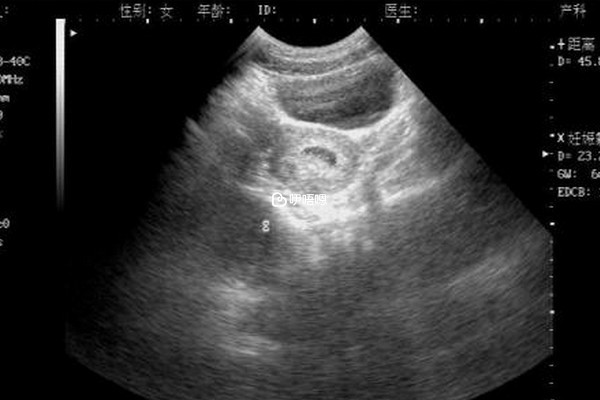

一般來說,懷孕第16周的時候,胎兒的生殖器才開始發育,孕婦可以通過彩超檢檢視到胎兒的外生殖器官,根據生殖器官判斷男女,另一種方法可以根據無創DNA檢查來檢查胎兒的性別,這種方法一般懷孕九周之後就可以看出,這有這些才有科學依據的方法,而網路上流傳的生男生女公式並不準確,孕婦不要太過當真,下面分享一下生男生女公式: